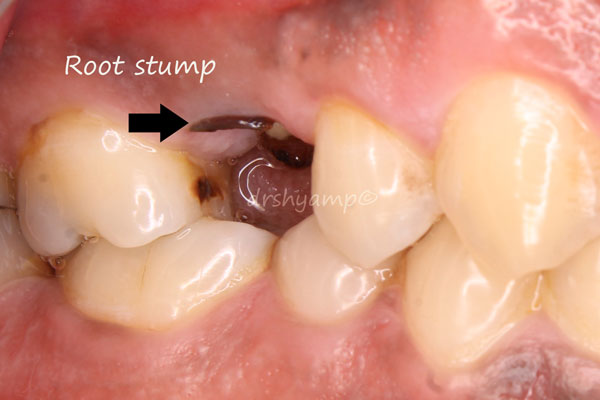

immediate dental implant

-

immediate dental implant

-